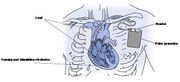

| 02:53, 6 August 2012 | ICD.jpg (file) |  |

67 KB | 1 | |